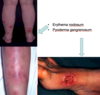

What are the 2 categories of extra-intestinal features of IBD (6-50% pts)?

How might IBD affect the skin?

Erythema nodosum (5-10% with acute IBD, swollen fat under the skin causing red bumps and patches), pyoderma gangrenosum (<5% - skin condition causing painful ulcers). [Pic]

How might IBD affect the eyes, joints and liver?

Eyes: episcleritis (benign, self-limiting inflammatory disease affecting episclera), uveitis (uvea inflammation - visible pus cells in anterior chamber of eye)

Joints: sacroilitis and anklyosing spondylitis, large joint arthropathy, small joint arthropathy

Liver: primary sclerosing cholangitis (bile duct inflammation - itching, jaundice, risk of cancer of bile duct and colon), fatty liver, autoimmune hepatitis. [Pic]